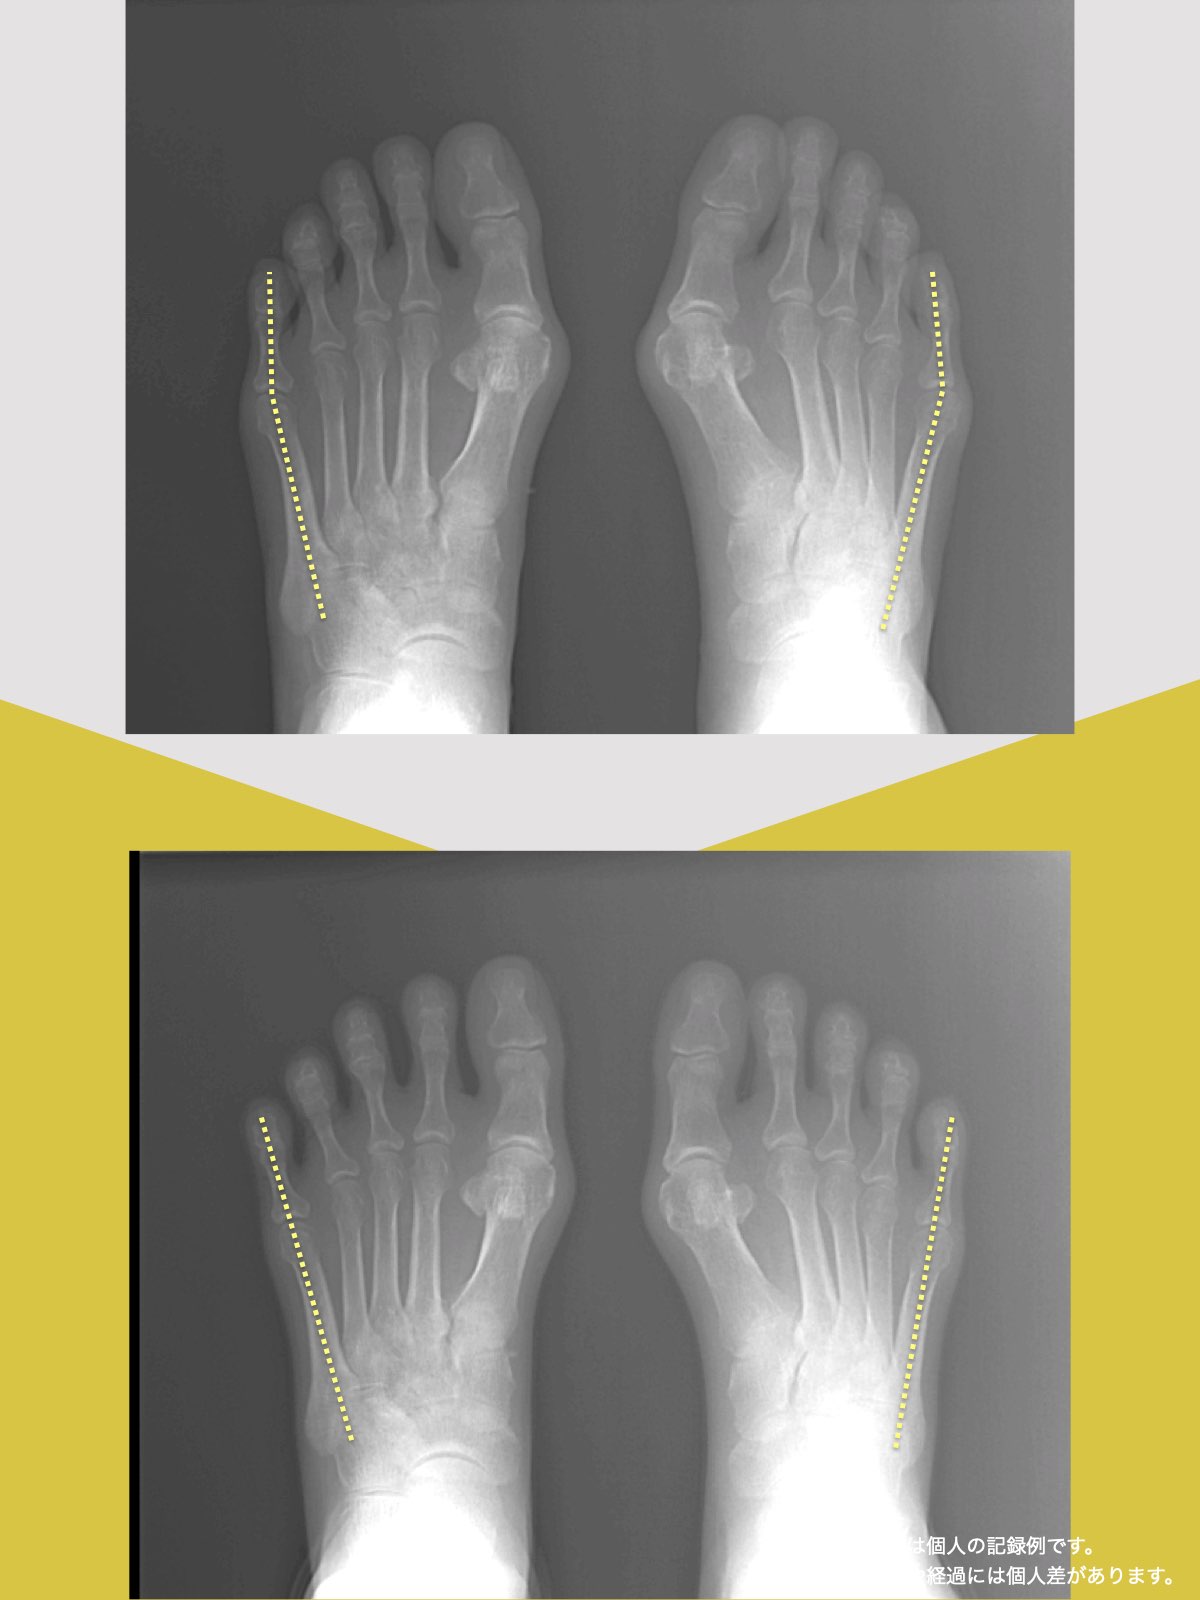

東京大学名誉教授・石井直方先生(運動生理学)とともに、2020〜2022年に行った共同研究では、YOSHIRO SOCKSの着用および、ひろのば体操を日常的に実践された方を対象に、内反小趾などに関する足指の状態や角度の変化について評価を行いました。

内反小趾角

開始時の内反小趾角は25.1°

8週間後の内反小趾角は5.3°

8週間目の平均値では、開始時と比べて、内反小趾角に19.8°の変化がみられました。

※開始前と8週間目の平均値の差

※グラフは臨床試験における平均値の推移を示したものです

※結果には個人差があり、すべての方に同様の変化が生じるわけではありません

※本データは石井直方名誉教授(東京大学)の助言を得て実施された研究に基づくものです